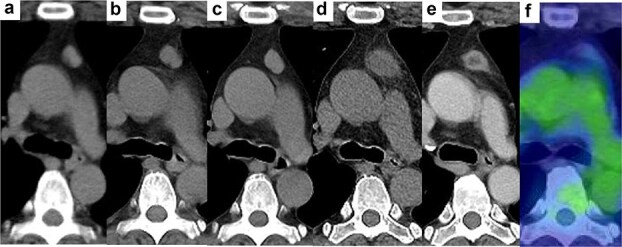

The causality of thymoma (TM) or thymic hyperplasia and various autoimmune diseases (AISs) remains poorly understood. To date, there have been no confirmed cases of pathologically complete regression of TM. We present a rare case of complete regression of an anterior mediastinal tumour secondary to the removal of metallic dental crowns as a treatment for metal allergy assessed to exacerbate pityriasis rubra pilaris, a rare cutaneous disease. After dental crown removal, the skin lesions improved, and the anterior mediastinal nodule (AMN) shrank rapidly through transient enlargement with a low density in the central area. Despite observation being an option, the patient preferred surgical resection and pathological examination, which revealed no remnant neoplasm. Treatment for skin conditions rarely induces complete regression of the AMN. This case highlights the potential novel link between anterior mediastinal tumours and AISs, including cutaneous disorders, and raises awareness amongst clinicians of this possible association.